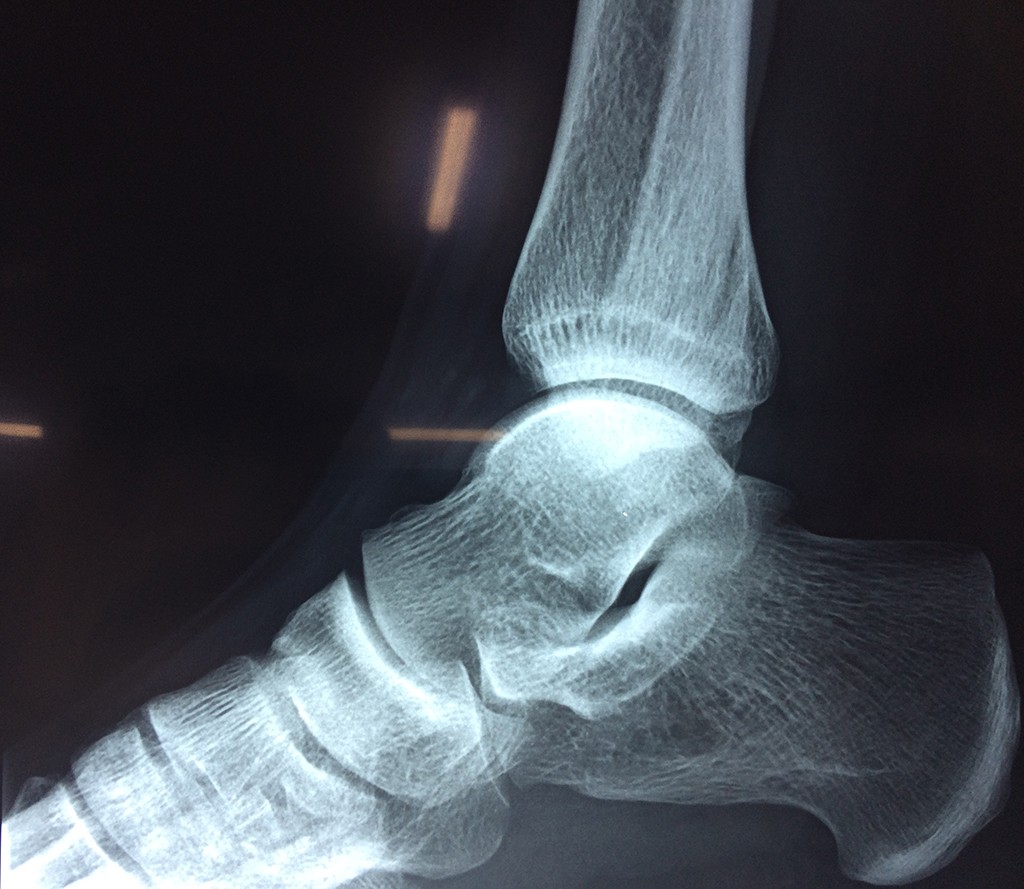

Una fractura de tobillo es la rotura de uno o más de los huesos del tobillo. Estas fracturas pueden ser:

Algunas fracturas de tobillo pueden requerir cirugía si:

- Los extremos de los huesos están desalineados entre sí (desplazados).